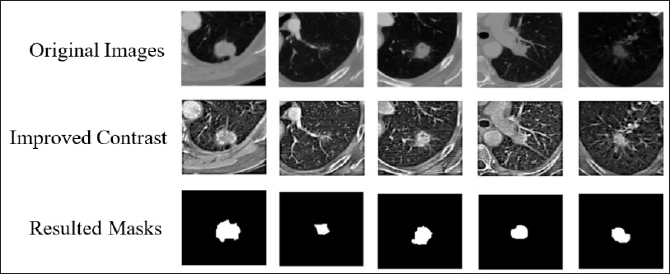

3.2. Preprocessing

Our preprocessing techniques were used to enhance the feature of the images, which in turn improve the performance of the detection and classification, by enhancing the contrast of specific ranges after adjusting the intensity levels according to local histograms [26], this stage involved the contrast limited adaptive histogram equalization (CLAHE) algorithm as shown in Fig. 5, which executed to enhance the contrast of each input image.

Fig. 5. Demonstrates the differences between the original images row (1) and the same images after applying contrast-limited adaptive histogram equalization row (2).

To improve the performance of preprocessing by adopting CLAHE to improve the input images contrast and certainly increases the accuracy and speed of nodule identification and reduce the computational load of network training and evaluation, therefore, to reduce the interference of unimportant lung regions processed on the evaluation outcomes, the obvious salient locations of each labeled image were cropped based on the node position provided in the annotation files, and the original image sizes were cropped to (96 × 96) pixels to retain the fully important private information as shown in Fig. 7.